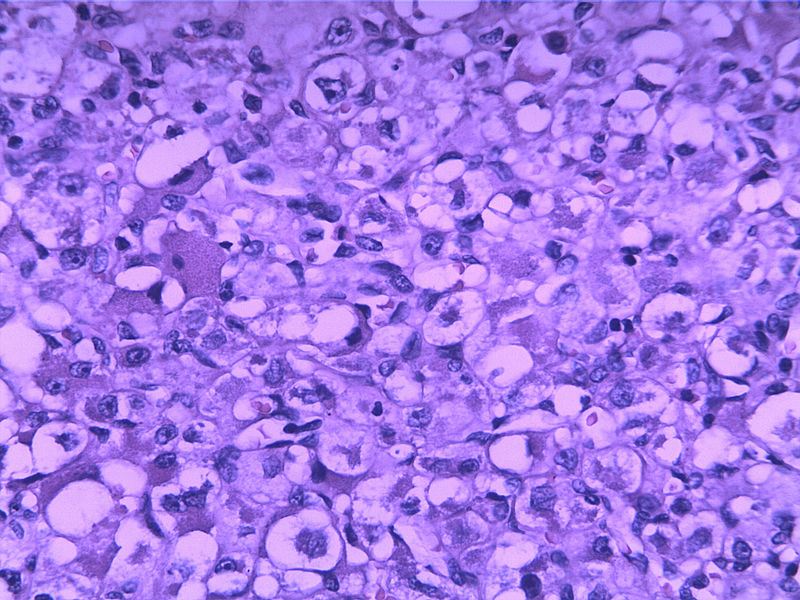

女30Y,大腿肿物5Y,直径3cm

• 女30Y,大腿肿物5Y,直径3cm图1

图1

多形性软组织肉瘤

1脂肪肉瘤

2横纹肌肉瘤

3上皮样肉瘤

您的诊断:

1)圆形细胞脂肪肉瘤?

2)腺泡状横纹肌肉瘤?

3)近端型上皮样肉瘤?

4)副神经节瘤?

5)腺泡状软组织肉瘤?

6)滑膜肉瘤?

7)恶性颗粒细胞瘤?

8)其他?

首选PEComa

圆形细胞脂肪肉瘤

图片不清楚,至少要考虑和排查脂肪肉瘤。

Pleomorphic liposarcoma

● Widespread high grade, pleomorphic tumor cells with some lipoblasts but no evidence of well differentiated liposarcoma

Micro description

● Well circumscribed but non-encapsulated with infiltrative borders

● At least focal typical liposarcomatous areas

● Pleomorphic cells cover > 65% of cut surface with MFH-like, round cell liposarcoma-like (without vascular network), spindle cell liposarcoma-like or epithelioid cells (Mod Path 1999;12:722)

● Usually high grade with enlarged round to bizarre nuclei; tumor necrosis common; median 25 mitotic figures/10 HPF

● May have neutrophils within giant cells, hemangiopericytic foci, extra- and intracellular hyaline droplets

腺泡状软组织肉瘤

生长位子比较深,浸润纤维间质之中,诊断圆形细胞脂肪肉瘤 ,查一下免疫组化,S-100,VimE。及PCK排除一下上皮来源的印戒细胞癌。

首选圆形细胞脂肪肉瘤。

本例可能是具有非典型性组织学特征的腺泡状软组织肉瘤

Enzinger and Weiss:The individual cells are large, rounded, or more often polygonal and display little variation in size and shape. They have distinct cell borders and one or more vesicular nuclei with small nucleoli and abundant granular, eosinophilic, and sometimes vacuolated cytoplasm. Mitotic figures are scarce. Rare pleomorphic tumors have been reported in the literature ——Evans HL: Alveolar soft-part sarcoma. A study of 13 typical examples and one with a histologically atypical component.  Cancer  1985; 55:912.

腺泡状软组织肉瘤的边缘常看见扩张的静脉,并常见脉管浸润,很类似于副节瘤或血管周细胞瘤